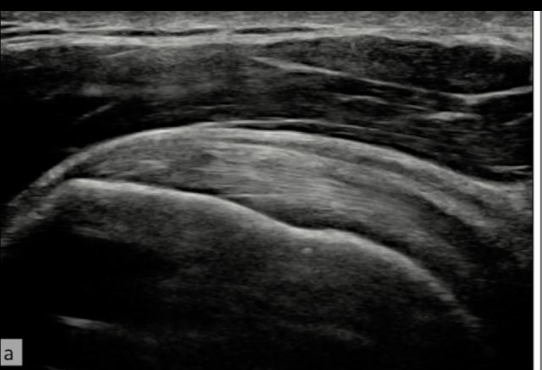

A

Normal

Deltoides

Bursa

Supraespinoso

Cartilago

Humero